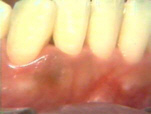

| Esta serie de

imágenes muestra el diagnóstico y tratamiento de la periodontitis

moderada en una mujer de 35 años de edad. Se observa

inflamación por el cambio de color, aspecto de la superficie y por la consistencia del margen gingival. Si el margen

gingival está flojo cuando aplicamos aire de la jeringa triple es una indicación de inflamación

del tejido. |

Note la

inflamación gingival y la presencia de placa supragingival en los

dientes. En bucal del segundo molar hay una bolsa profunda al

sondaje y placa supra y subgingival al movimiento lateral de la sonda. |